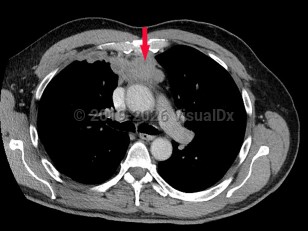

Imaging Studies image of Thymoma - imageId=6841586. Click to open in gallery.  caption: '<span>Contrast enhanced CT scan of chest with anterior mediastinal mass. <br /></span>'

Contrast enhanced CT scan of chest with anterior mediastinal mass.